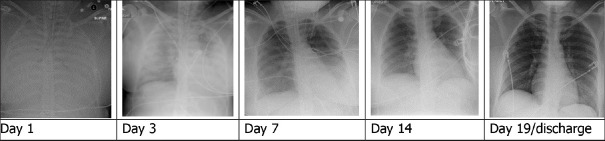

Materials and methods: We identified 28 patients requiring VV ECMO cannulation for influenza-related ARDS between September 2009 and January 2018. Interpretation of chest X-ray images was divided into zones that correspond to anatomical lobes on computed tomography. Progression of radiologic injury was assessed by analysing the number of zones involved on the chest radiograph (X-ray) at days 1, 3, 7, 14, and 21 from cannulation and discharge. The primary endpoint was survival to hospital discharge.

Results: The majority of patients had complete opacification on days 1, 3, and 7 after VV ECMO cannulation. Patients with persistent complete opacification on chest X-ray infiltrate by day 14, following cannulation had an increased mortality. Survival to hospital discharge was increased in patients demonstrating improvement in radiological findings at day 19 compared to patients without significant radiologic improvement (100% vs 53%, log-rank P = 0.003).

Conclusion: The evolution and recovery of lung injury reflected by serial chest X-ray imaging studies after influenza-related ARDS requiring VV ECMO support is associated with improved survival in this single centre, retrospective cohort.